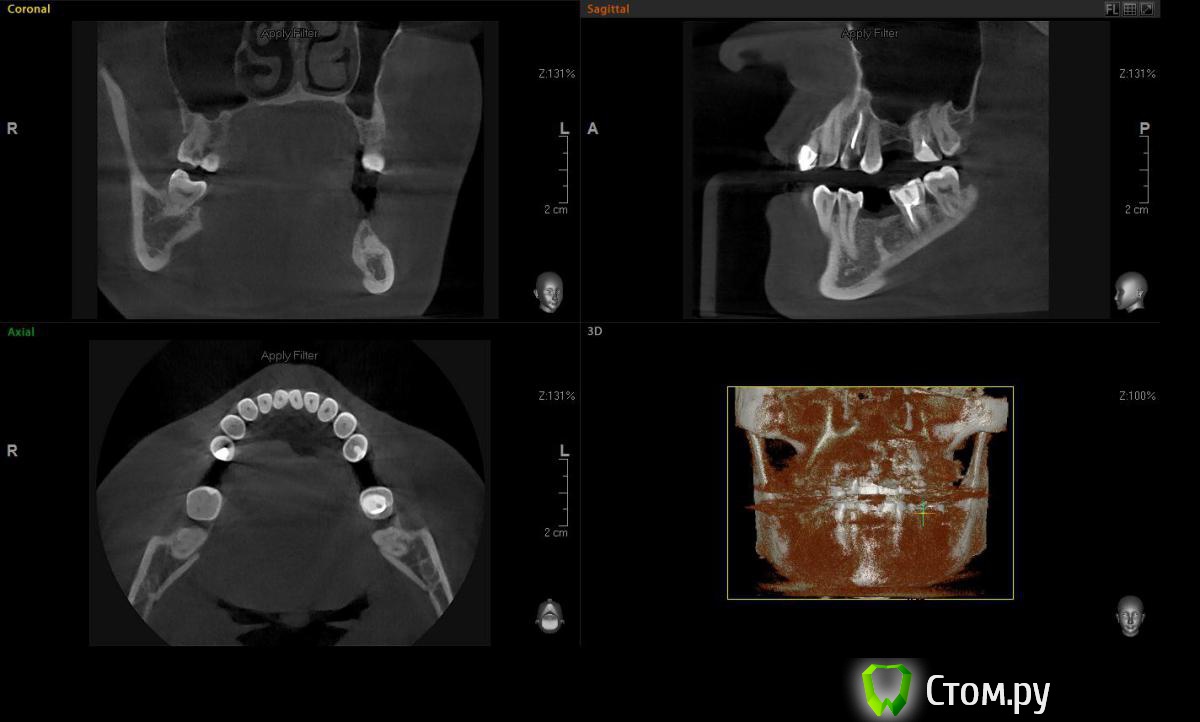

Евгений Ходыкин Опубликовано 19 октября, 2014 Поделиться Опубликовано 19 октября, 2014 Всем привет. Кто сталкивался подскажите плиз что за образование и как отразится на постановке имплантата. Вроде подобное что-то обсуждалось, но перестрахуюсь Ссылка на комментарий

Чертков Александр Опубликовано 20 октября, 2014 Поделиться Опубликовано 20 октября, 2014 Остеома или конденсирующий остит. На имплантацию никак не повлияет. Повлияет вестибулярный дефект гребня 2 Ссылка на комментарий

Михаил Демурчян Опубликовано 24 октября, 2014 Поделиться Опубликовано 24 октября, 2014 (изменено) Похоже на гиперцементоз. Возможно также, имеется осколок корня удаленного 3.6. Изменено 24 октября, 2014 пользователем Михаил Демурчян Ссылка на комментарий